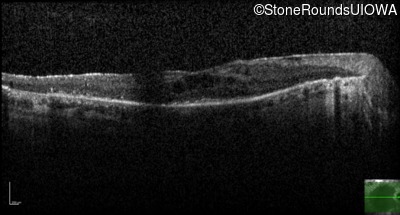

Age at visit: 46 years

This 46 year old man has had poor vision in dim light since age 2.

Diagnosis & molecular findings

AR Retinitis Pigmentosa SLC24A1 Met252 del2ggaAT Leu1052 del2ctTC AR